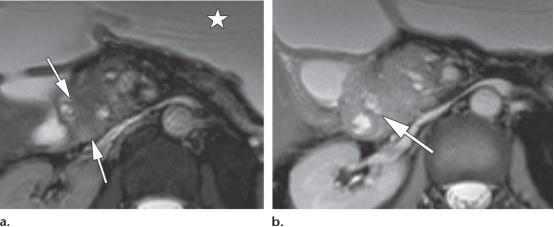

35岁女性,1型自身免疫性胰腺炎,(a图)轴位T2WI示低信号纤维化边缘(白色长箭头),(b图)轴位增强磁共振示均匀强化的胰腺以及不强化的纤维边缘(白色长箭头)。

39岁男性,1型实性十二指肠旁胰腺炎(PDP,即沟槽性胰腺炎)

(a图,b图)轴位CT示边界不清的低密度肿物样病变,位于十二指肠胰腺沟内(白色长箭头),胰头区可见散在的胰腺实质钙化灶。

(c图)冠状位CT图示十二指肠沟内肿物样病变(白色长箭头),以及十二指肠壁的囊性变(白色五角星),胆总管远端部分可见。

(d图)磁共振胆胰管成像示胆总管远端局灶狭窄(白色长箭头),胰腺分支胰管略微显著(白色短箭头),注意观察十二指肠胰腺沟的增宽,以及十二指肠壁的囊性变(白色字母d)。